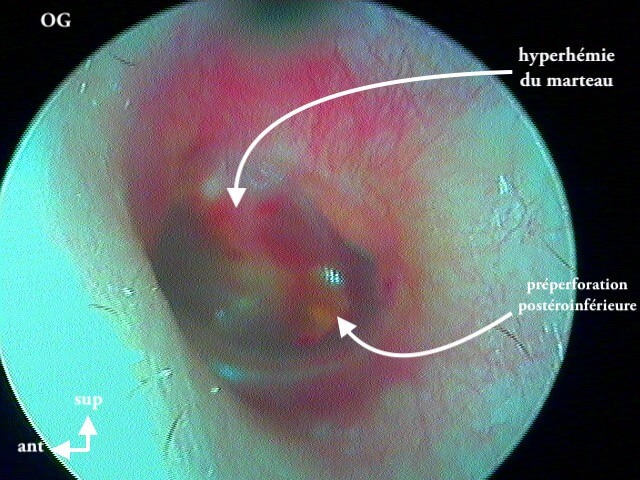

3/2 barotraumatique

– stade I : hyperhémie du manche du marteau et de la pars flaccida ;

– stade II : tympan rétracté, congestif, immobile

– stade III : aspect d'otite séromuqueuse

– stade IV : aspect otite séro-hémorragique, otohématome

– stade V : perforation

Ici des stades V perforés